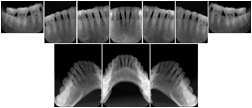

3. A dental provider wishes to capture a series of DICOM IO images for the patient’s dentition. The tooth morphology, teeth are divided into molars, premolars, canines and incisors, and a number of images for each jaw. The anatomic information was captured utilizing the triplet of schema. This standard code sequence is based on ISO 3950-2010, Dentistry - Designation system for teeth and areas of the oral cavity.

Every IO image should have anatomic information either through the primary or modifier sequence.

In most standard cases, images are oriented in structured layouts. These structured displays are useful to be shared between providers for reference purposes.

Table OO.1.1-1 shows structured display standard templates, where Viewset ID is based on the Japanese Society for Oral and Maxillofacial Radiology (JSOMR) classification provided by JIRA (Japan Medical Imaging and Radiological Systems Industries Association, www.jira-net.or.jp). Expected or typical teeth to be imaged location, region and designation codes are based on ISO 3950-2010, Dentistry - Designation system for teeth and areas of the oral cavity. For all the hanging protocols listed in OO.1.1-1, the value to use for Hanging Protocol Creator (0072,0008) is "JSOMR" and the value to use for Hanging Protocol Name (0072,0002) does not include "JSOMR" (e.g., "DL-S001A", not "JSOMR DL-S001A").